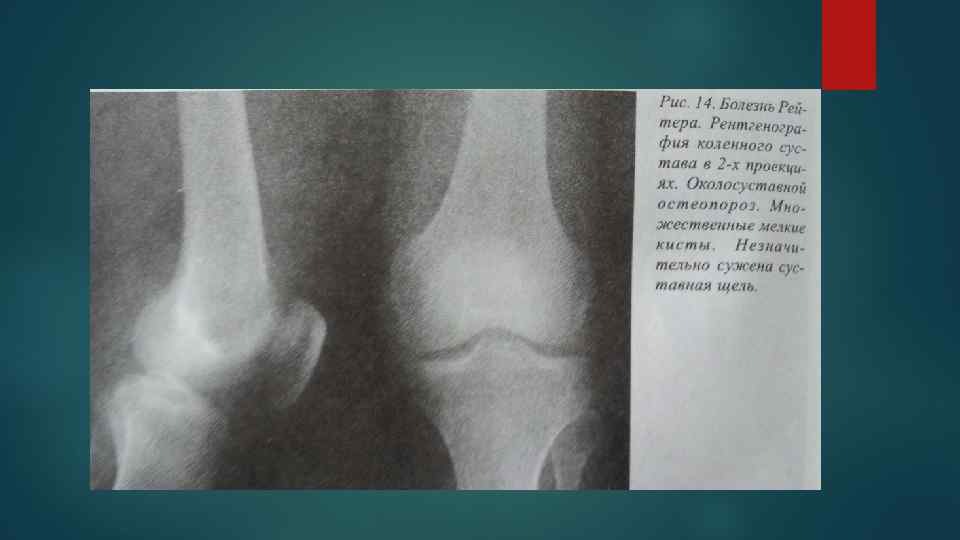

Рентгенологические изменения поражения суставов при болезни Рейтера Рентгенологические изменения поражения суставов при болезни Рейтера

Типичным для болезни Рейтера является несимметричная распространенность изменений с преобладающим вовлечением в патологический процесс Типичным для болезни Рейтера является несимметричная распространенность изменений с преобладающим вовлечением в патологический процесс костей и суставов нижних конечностей. Наиболее характерными местами изменений являются мелкие суставы дистальных отделов стоп, пяточной кости, коленные и голеностопные суставы. Реже обнаруживаются в осевом скелете, крестцовоподвздошных суставах и симфизе.

Утолщение мягких тканей связывается с внтурисуставными изменениями, периартикулярным отеком мягких тканей и воспалительными Утолщение мягких тканей связывается с внтурисуставными изменениями, периартикулярным отеком мягких тканей и воспалительными изменениями в слизистых сумках и сухожилиях. Околосуставной остеопороз Сужение суставных щелей в суставах дистальных отделов стоп. Эрозии первоначально появляются на краях суставных поверхностей, позже процесс может прогрессировать и вовлекать субхондральный отдел кости в центральной части сустава Периоститы линейные и бахромчатые